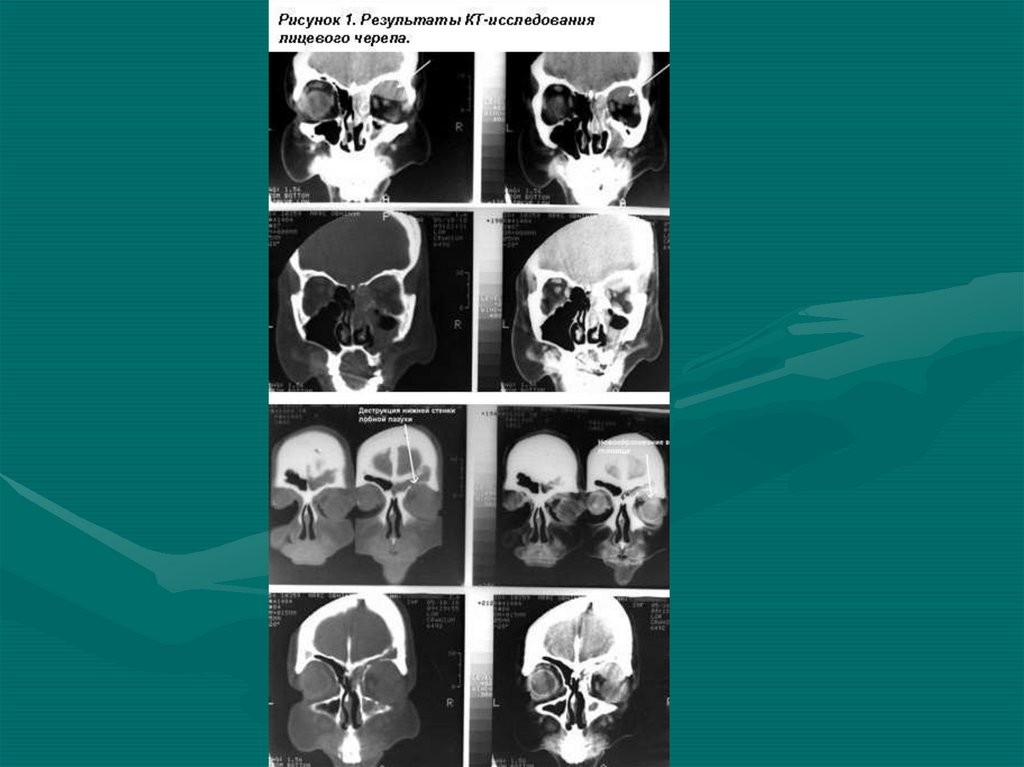

9. Рентгенорадиологическая группа

• Рентгенограмма простая

• Рентгенограмма с контрастным веществом

(вентрикулография, ангиография,

миелография)

• Простая и компьютерная

рентген-томография